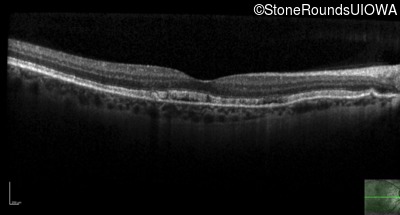

Age at visit: 57 years